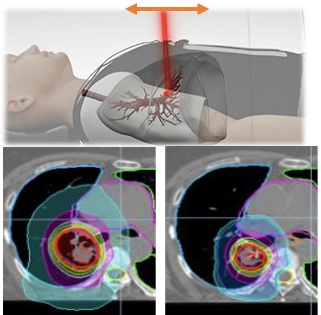

●強度変調放射線治療(IMRT)

強度変調放射線治療(IMRT)とは、3次元的に複雑な線量分布を作成するためにコンピュータを使用して計算を行い、照射野内の放射線の強度を変化させながら多方向から照射を行う技術です。

腫瘍や正常組織の形、大きさ、場所に応じて、凹凸のある放射線強度を正確に3次元で設定することができます。

当院に導入された装置は2台ともこのIMRTに対応しています。

| ○当院に導入されているRadixact X9は強度変調放射線治療専用機で従来型の放射線治療用照射装置と比較 しより複雑な線量分布にて照射を行う事が可能となっています。

以下の技術も導入されています。 | |

| ●動態追尾システム Synchrony® 呼吸などで移動する腫瘍を呼吸追尾カメラと標的検出用のX線装置で把握し、リアルタイムに追跡しながら照射します。 放射線照射範囲を最小限にすることができ、より副作用の少ない安全な治療が可能になります。 肺癌のように腫瘍が動く部分では特に有効とされます。 |